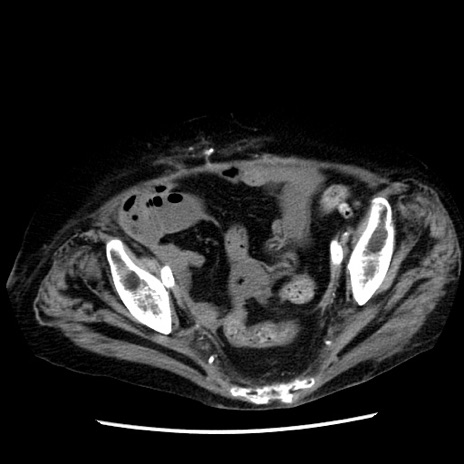

症例14(横断像)

【症例】 90歳代女性

【主訴】 腹痛・嘔吐

【現病歴】今朝から左側腹部痛を認めた。 経過観察していたが、嘔吐を認めたため来院。

【既往歴】 子宮癌術後

【身体所見】 意識清明、BP 127/54mmHg、P 98bpm Sp02 95%(RA)、BT 35.8°C、腹部平坦・軟腸ぜん動音聴取良好、右下腹部圧痛(+) 反跳痛なし

【データ】WBC 9800、CRP 0.46